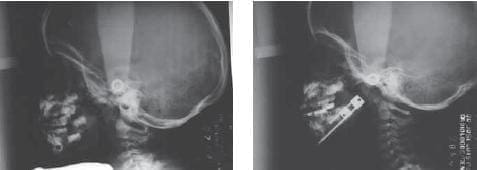

Cefalometría Pre y Post Distracción.

Planorex Pre y Post Distracción